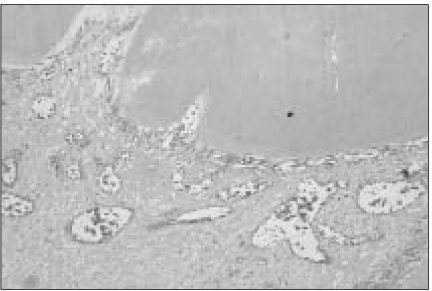

Original Article Pulp response of mineral trioxide aggregate, calcium sulfate or calcium hydroxide